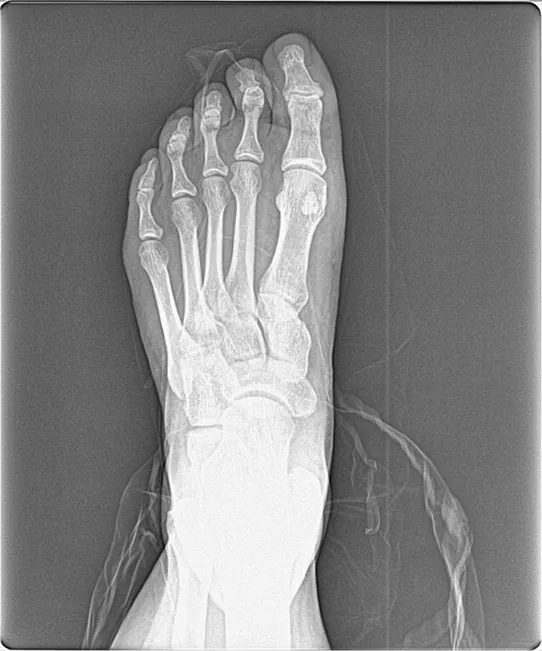

X-ray of foot Tailor’s bunions, sometimes called "bunionettes," are a variation on more common bunions, which appear on the inside of the foot, under the big toe. Tailor’s bunions instead develop on the outside of the foot, under your smallest toe. Like bunions, tailor’s bunions rub against your shoes and can create redness and swelling.